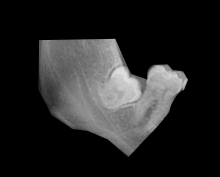

Für den, der zuletzt kommt, wird es mitunter eng. Dies gilt auch für Zähne, insbesondere wenn im Alter von 16-20 Jahren die so genannten Weisheitszähne in den hinteren Bereichen von Unter- und Oberkiefer durchbrechen.